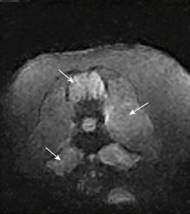

Žáková M. Ischemické príhody spôsobujúce spinálne a neuromuskulárne problémy u psov. ČasťII: Ischemická neuromyopatia- popis prípadu. Veterinární klinika 2026;23:13-19. SOUHRNV tomto článku je prezentovaný prípad psa s perakútnym nástupom paraplégie v dôsledku aortálnej tromboembólie. Jedná sa o veľmi netypický priebeh tohto ochorenia u psov. Prevedenou diagnostikou bol identifikovaný tromboembolus v…